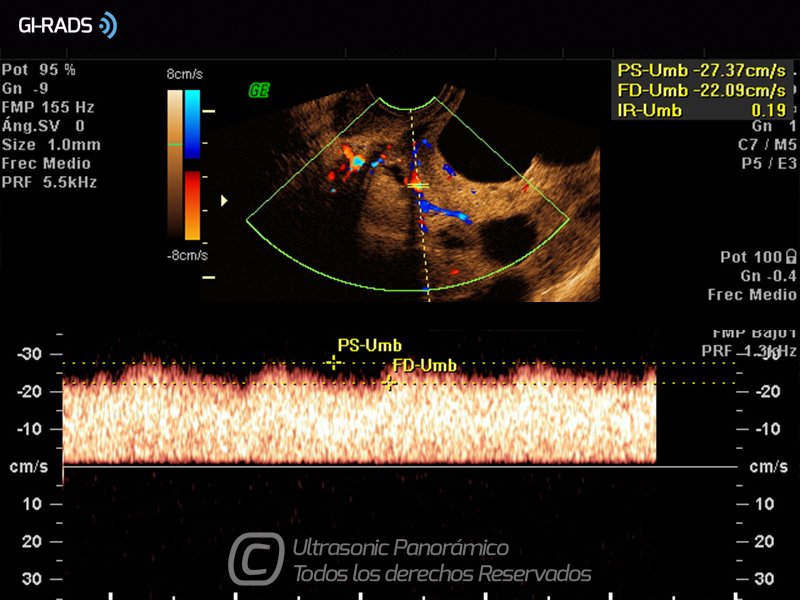

Cáncer Anexial – Baja Resistencia

• Cáncer Anexial – Baja Resistencia